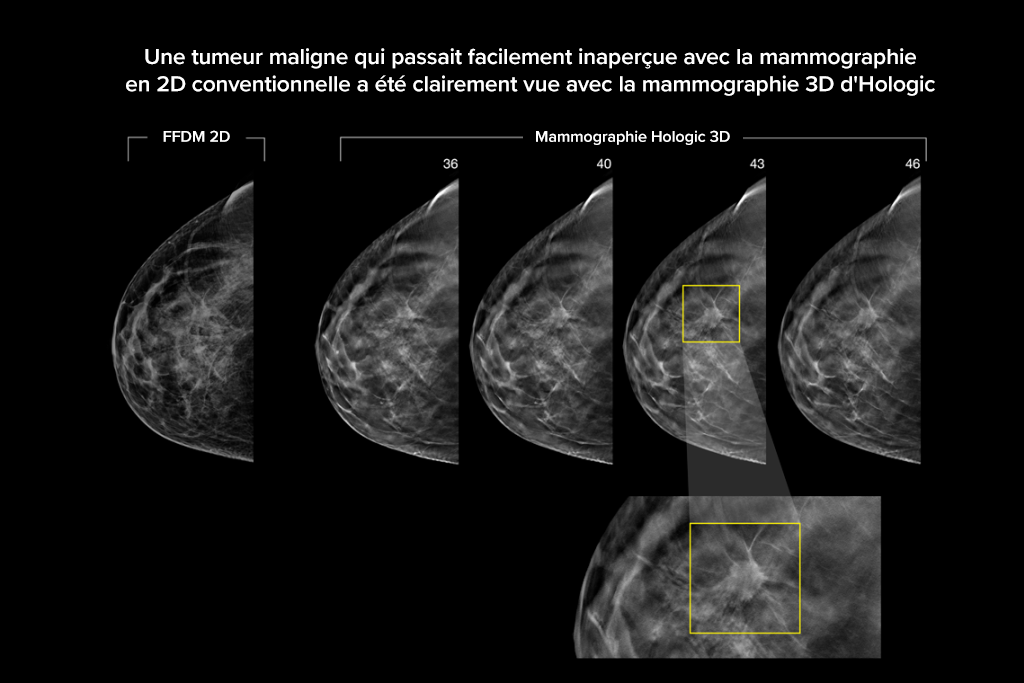

Images cliniques

Images cliniques d’une mammographie

Images cliniques d’une mammographie avec lésion suspecte

Images cliniques d’une mammographie sur un sein graisseux